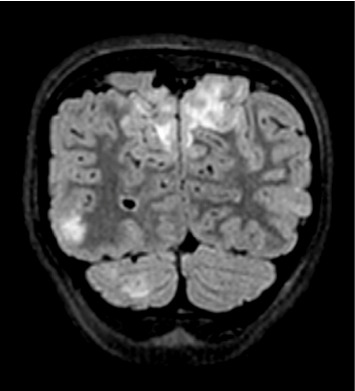

History: An 8-year-old previously healthy female presented to the emergency department after new-onset seizure activity. Three days prior, she experienced severe headaches and rash over her left lower extremity. She developed nonbilious, nonbloody emesis on the day prior to admission. The morning of presentation, she was found unresponsive, exhibiting right gaze deviation and clenched jaw concerning for seizure activity. Further history revealed recent Group A streptococcal pharyngitis, which had been treated with a 10-day regimen of amoxicillin. During this time, her mother reported decreased oral intake but normal urinary output, without dysuria or hematuria. Physical Examination: Vital signs were notable for temperature of 101.7 degrees Fahrenheit, heart rate of 100 beats per minute, blood pressure of 167/97, respiratory rate of 28, and oxygen saturation of 96% on room air. The patient was drowsy but arousable. Her neck was supple without evidence of meningismus. A skin exam revealed an erythematous, crusting rash, resembling contact dermatitis on the left lower extremity below the knee. The patient was somnolent but oriented to self and able to follow simple commands. Cranial nerves II-XII were intact bilaterally. Sensory, motor, and coordination were unremarkable. Laboratory, Imaging, and Procedures: Laboratory findings included leukocytosis, microscopic hematuria, decreased C3 and C4 levels, and positive antistreptolysin O (ASO) titers. A lumbar puncture was conducted with unremarkable cerebrospinal fluid (CSF) indices. Imaging revealed hypoattenuation in the occipital lobes on computed tomography (CT) venogram and hyperintensities in bilateral occipital lobes on magnetic resonance imaging (MRI) T2 fluid-attenuated inversion recovery (FLAIR) sequences, consistent with posterior reversible encephalopathy syndrome (PRES). Discussion: PRES in pediatric patients has been associated with a variety of conditions including hypertension (idiopathic or secondary), renal disorders, autoimmune disorders, and hematologic or oncologic conditions. However, PRES secondary to acute postinfectious glomerulonephritis (PIGN) is rare. Hematuria on the urinalysis led to obtaining complement levels, and further elucidation of history helped to narrow the differential to PIGN due to streptococcal infection with confirmatory positive ASO antibody titer. This case highlights a rare sequala of a commonly seen pediatric infection.